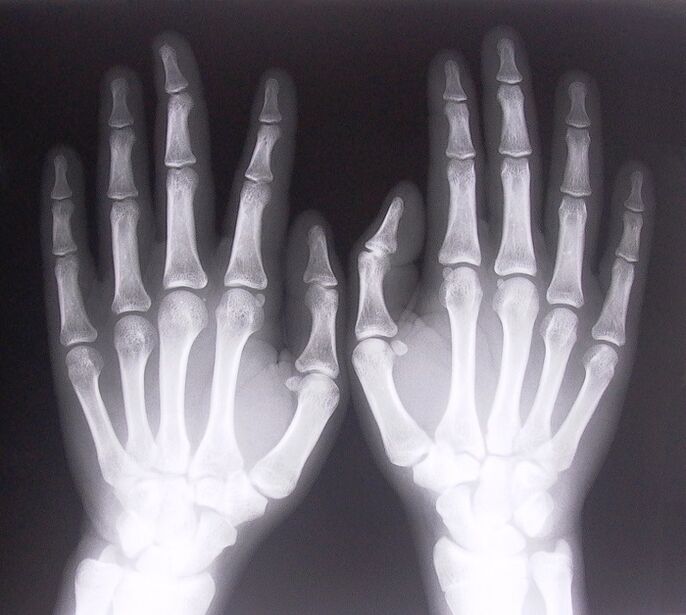

1. Take x-rays.

X-ray as a method of diagnosing finger joint pain